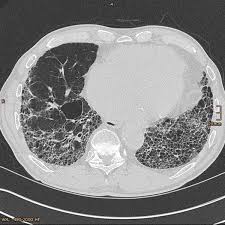

Drug-induced interstitial lung disease DIILD represents a rare but potentially fatal adverse drug reaction. The high-resolution CT findings of chemotherapeutic druginduced lung disease reflect the histologic findings. Broadly certain drug classes tend to cause similar overlapping patterns of.

Chemotherapeutic Drugs As many as 10 of patients receiving che-motherapeutic agents will develop an ad-verse drug reaction in their lungs 2. A large number of drugs have been implicated to have this potential risk including chemotherapeutics and disease-modifying antirheumatic drugs. Drug-induced interstitial lung disease DILD is not uncommon and has many clinical patterns ranging from benign infiltrates to life-threatening acute respiratory distress syndrome.